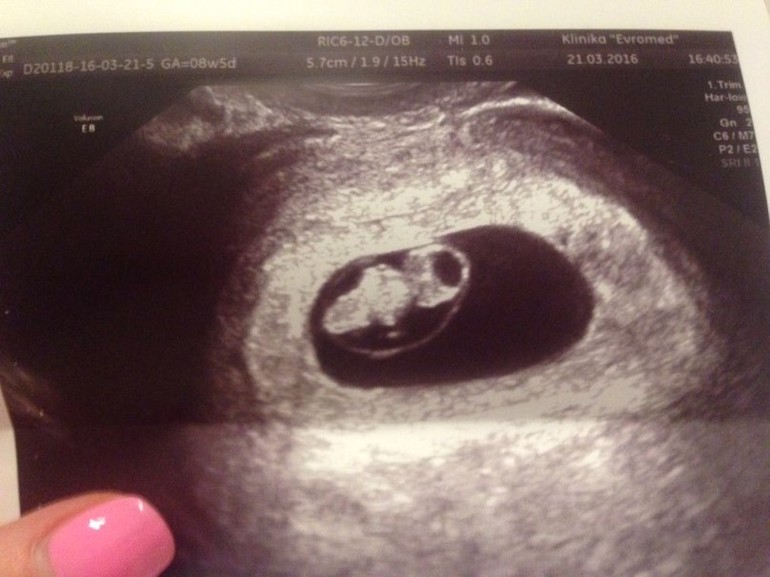

6. Первый ультразвук. Беременность маточная! Визуализируется яйцо) Эмбрион в нём)

7. Снова УЗИ. Этот гулкий звук биения маленького сердечка отпечатался в моем сердце на всю жизнь